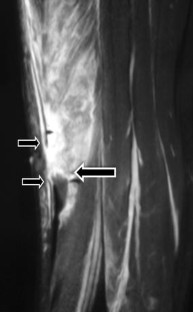

Fig. 1

Fig. 2

Fig. 3

Fig. 4